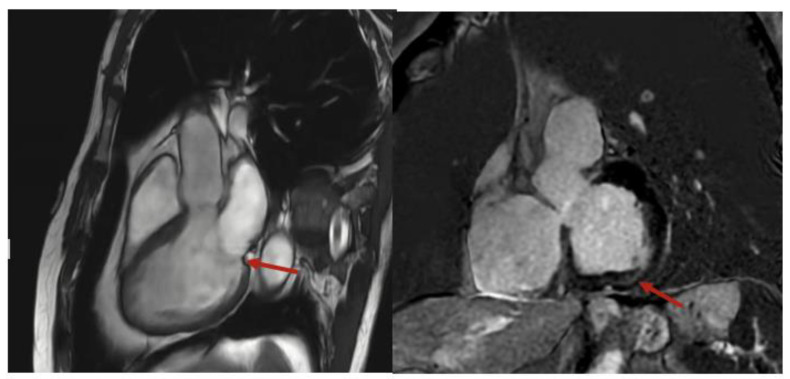

Background and Clinical Significance: Mitral valve prolapse (MVP) is commonly benign, but may result in life-threatening arrhythmias and sudden cardiac death (SCD). Mitral annular disjunction (MAD) often coexists with mitral valve prolapse (MVP) and has been implicated in the development of ventricular arrhythmias through myocardial stretch and fibrosis. Case Presentation: Here, we present a case that highlights the diagnostic value of multimodal imaging in evaluating ventricular ectopy in the context of MVP and MAD. A 72-year-old male presented to the cardiology clinic with palpitations and fatigue, compounded by an arrhythmia identified by his Apple Watch. Holter monitoring revealed premature ventricular contractions (PVCs), with cardiac magnetic resonance imaging (CMR) demonstrating MAD and basal inferolateral scarring. Despite minimal symptoms and normal echocardiographic imaging, CMR findings highlight the utility of advanced cardiovascular imaging in patients with newly detected ventricular arrhythmias. Conclusion: This case highlights the importance of integrating consumer wearables and advanced imaging in evaluating ventricular ectopy and its evolving role in risk stratification for patients with MVP, even in the absence of overt symptoms.